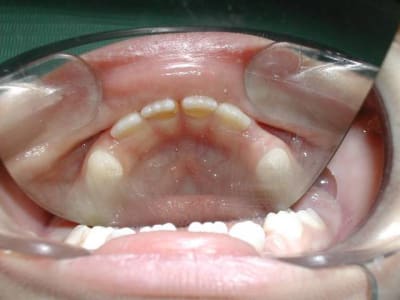

J'ai une petite patiente de 8 ans qui a 54 et 64 à l'état de racines car apparemment elles n'avaient été reconstituées qu'au cavit dans un autre cabinet au lieu de coiffes. Résultat:je vais devoir extraire et faire des mainteneurs d'espaces. Question: est-il mieux de faire 2 mainteneurs unilatéraux ou un seul bilatéral? J'ai déjà entendu des dentistes qui plutot que de mettre un mainteneur d'espace préféraient laisser la dent telle quelle malgré un délabrement très important pour maintenir l'espace, ce qui est manifestement le cas de ma patiente. C'est vrai qu'il y a très peu de cabinets où ils font des endo sur dents temporaires!

Me revoilà avec mon mainteneur d'espace. Finalement j'ai réalisé l'endo sur 64 et je vais posé le mainteneur d'espace au niveau de 54 mercredi. LE praticien qui s'est occupé de ma petite patiente avant moi, avait manifestement extrait la couronne de 54 mais il reste les racines. Comme le germe de 14 n'est pas très loin sur la radio je me demande s'il ne serait pas mieux de les laisser se résorber plutôt que d'essayer de les retirer, sachant qu'elles sont en partie sous-muqueuses. Qu'en pensez-vous?